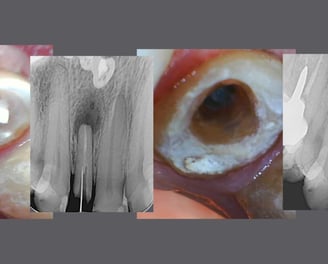

Adequação para futura prótese

Remoção de pinos, blindagem de canais e/ou da câmara pulpar, preparo do espaço para pino, reembasamento/confecção de provisórios, de acordo com a solicitação do indicador